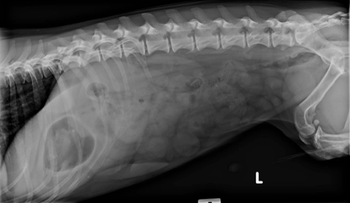

This diagnostic tool can provide a wealth of information about the structure and function of the respiratory tract.

Esophageal diseases are an important cause of dysmotility and regurgitation in dogs and cats. Here’s what you should know about these disorders.